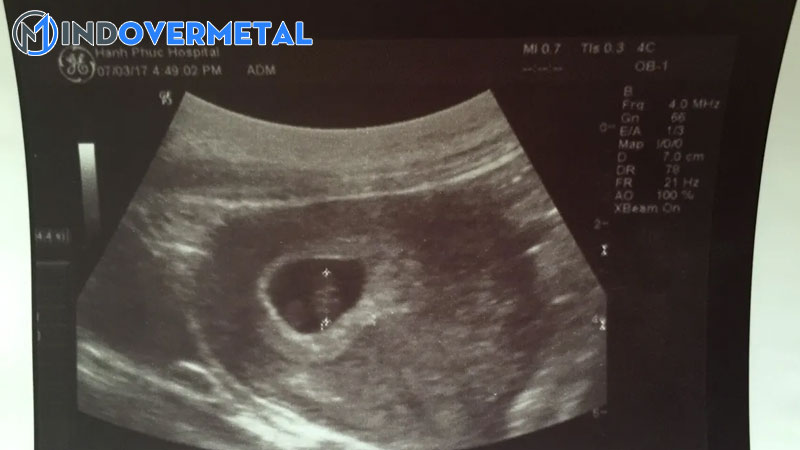

Việc siêu âm có túi thai nhưng chưa thấy phôi thai ở tuần thứ 5 là thông thường, bác sĩ sẽ khuyên mẹ nghỉ ngơi khoảng chừng 1-2 tuần rồi kiểm tra tiếp hoặc ngay khi có những bộc lộ không bình thường như ra huyết, đau bụng. Tùy từng hiệu quả siêu âm kiểm tra lại, nếu vẫn chưa có phôi thai, bác sĩ sẽ tìm nguyên do và cho mẹ giải pháp hài hòa và hợp lý nhất

Việc siêu âm có túi thai nhưng chưa thấy phôi thai ở tuần thứ 5 là thông thường ( Ảnh minh họa )